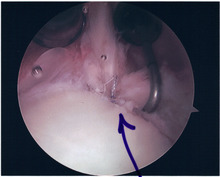

Repair of SLAP Tear

Arthroscopic SLAP Lesion (type 2) repair

Following inspection and determination of the extent of injury, the basic labrum repair is as follows.

• The glenoid and labrum are roughened to increase contact surface area and promote re-growth.

• Locations for the bone anchors are selected based on number and severity of tear. A severe tear involving both SLAP and Bankart lesions may require seven anchors. Simple tears may only require one.

• The glenoid is drilled for the anchor implantation.

• Anchors are inserted in the glenoid.

• The suture component of the implant is tied through the labrum and knotted such that the labrum is in tight contact with the glenoid surface.